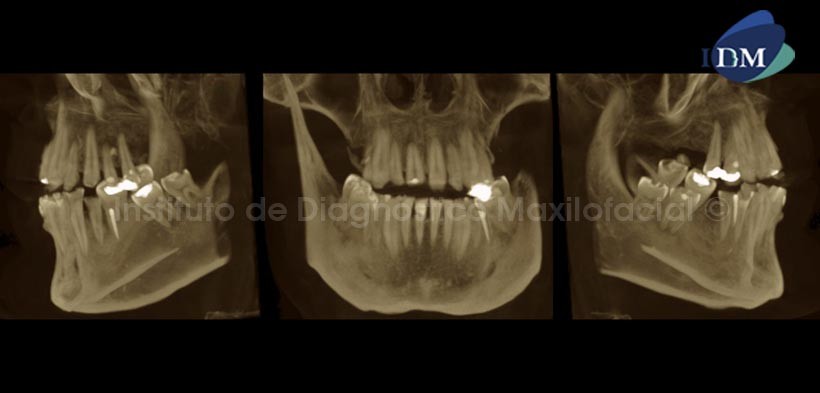

En cortes transaxiales (Fig.3 y 4) se observan diferentes piezas dentarias, notando el delgado grosor del esmalte en todas ellas, además se observan cavidades, las cuales pueden estar asociadas a este tipo de anomalía.